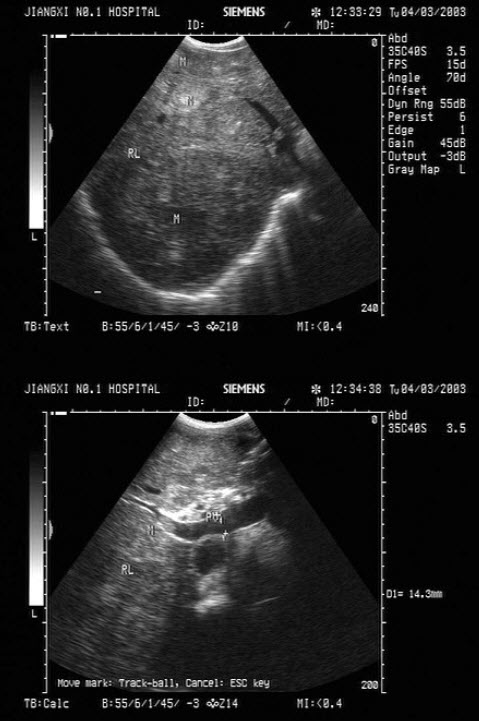

3、单项选择题

男,18岁,外伤1小时就诊。结合超声声像图,诊断为()

A.脾外伤血肿

B.脾淋巴管瘤

C.膈下积液

D.脾皮样囊肿

E.脾血管瘤